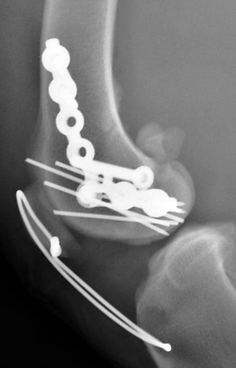

Major injuries to the stifle’s key structures almost always require surgery. Depending on the nature of the damage, various reconstruction techniques may be used. Postoperative immobilization with a splint or external frame is often necessary to protect the repair during recovery.

Prompt surgical intervention is critical to restore stability, reduce pain, and prevent further damage. Successful outcomes depend on the experience and skill of a surgeon with detailed knowledge of knee mechanics and anatomy.

Complex stifle trauma repair.